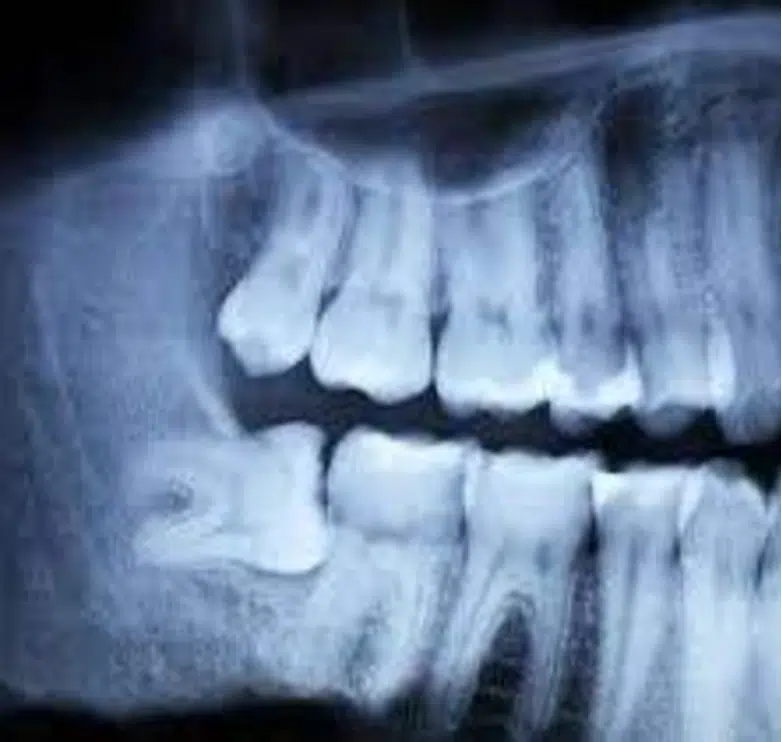

Hoeveel verstandskiezen zijn er?Er kunnen in totaal vier verstandskiezen zijn (twee in elke kaak, twee aan elke kant), hoewel in zeldzame gevallen ook de zogenaamde 'negende' of extra verstandskiezen aanwezig kunnen zijn . Het komt echter steeds vaker voor dat er geen vier verstandskiezen zijn, maar bijvoorbeeld drie, twee of helemaal geen . Dit groeiende fenomeen weerspiegelt onze evolutionaire ontwikkeling : verstandskiezen zijn in feite een erfenis van onze voorouders die sterke tanden, zoals kiezen, nodig hadden om vlees, rauw en hard voedsel te kauwen. Ons huidige dieet vereist deze sterke ondersteuning bij het kauwen niet meer, en daarom zullen verstandskiezen in de toekomst waarschijnlijk verdwijnen ! "Ze vertelden me dat ik al mijn verstandskiezen nog heb, maar ze zijn nog niet doorgekomen. Is dat normaal?"De aanwezigheid van verstandskiezen wordt meestal door de tandarts vastgesteld tijdens een mondonderzoek met behulp van een panoramische röntgenfoto. Hoewel ze aanwezig kunnen zijn, hoeven ze echter niet per se door te breken in de kaak . Vaak komen verstandskiezen, door een afwijkende positie of ruimtegebrek , niet door en blijven ze ingekapseld in het bot en onder het tandvlees, of komen ze slechts gedeeltelijk door. In sommige gevallen kunnen de onderste verstandskiezen in de kaak bijvoorbeeld een horizontale positie aannemen en naar de naastgelegen tand gericht zijn, waardoor ze niet de nodige kracht kunnen vinden om door te breken. | ![]() |

Voordat een achtste deel van de verstandskies wordt getrokken, voert de tandarts diagnostische tests uit, zoals een panoramische röntgenfoto of mogelijk een CT-scan , om de positie van de kies ten opzichte van de zenuwstructuren te beoordelen.